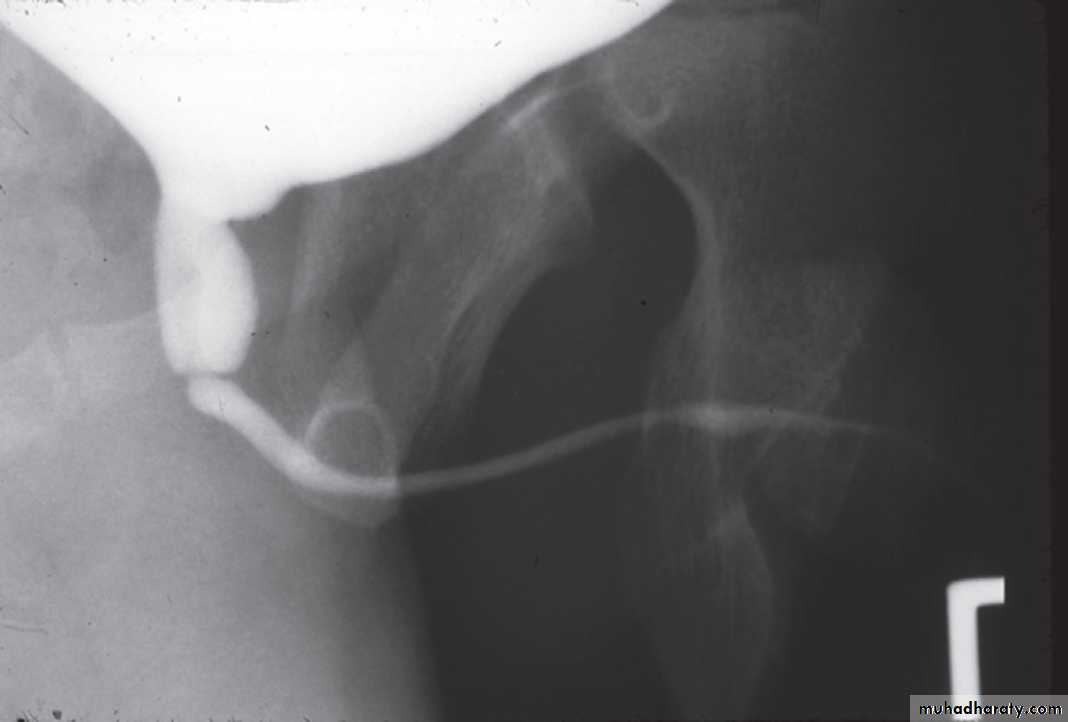

Ultrasound: The classic ultrasound findings in patients with PUV include bilateral hydroureteronephrosis, distended bladder, dilated posterior urethra, and a thickened bladder wall.Voiding Cystourethrography VCUG: it defines the anatomy of the bladder, bladder neck, and urethra.

PUV (VCUG)PUV (VCUG)